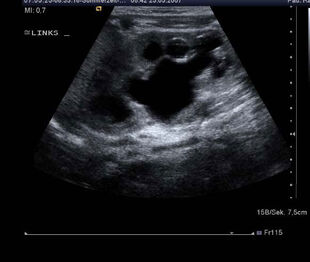

Die Ureterocele ist eine angeborene Missbildung des unteren Anteils des Harnleiters, der in die Blase mündet. Hat ein Mensch eine Ureterocele, dann bläht sich der unterste Anteil des Harnleiters in...